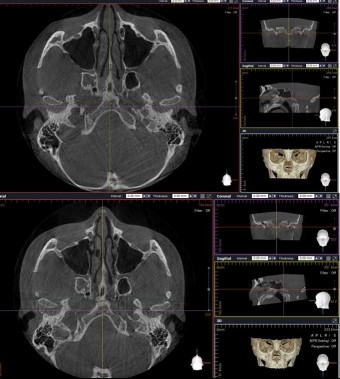

Not long ago, a practicing physician from Prague visited my clinic during orthodontic bracket treatment. She was diagnosed with facial asymmetry and body misalignment, and experienced MCB splint therapy. She was aware that bodily misalignment is related to asymmetry in the facial bones.

There are many around the world—including in Korea—who claim not only to treat TMJ or craniofacial structures, but to treat systemic disorders. Most of them use applied kinesiology for diagnosis and treatment. I myself served for five years as a dental director in a Korean applied kinesiology organization. It is a good discipline. Yet many people—including in Korea—have not gone beyond the level of using applied kinesiology. For example, in the case of the TMJ: applied kinesiology can determine which side of the joint is problematic, and can evaluate how effective a TMJ device is. However, it cannot reveal the direction of asymmetry between the right and left TMJs, or the detailed joint motion. The way to know those is through osteopathic medicine. In Korea, there is almost no practice of osteopathy. 99% of the population do not know the word “osteopath,” and few have experienced osteopathic treatment. It takes a long time to understand the motility of the TMJ.

I have devoted my life to performing orthodontic treatment for people with TMJ problems. Even in the United States, where osteopathy was born and has developed, it seems that almost no one applies the concept of osteopathy when fabricating splints for the TMJ.

Dentistry still remains dominated by the concept of CR (Centric Relation). Many osteopathic physicians have long claimed that the temporal bones move, and treat on that basis, yet the mainstream thinking has not changed. Many dentists still believe that if the mandible (lower jaw) is asymmetric or if the lengths on the right and left differ, surgery is required, and they in fact treat by surgery.